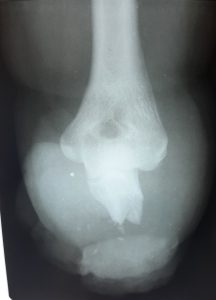

From the first days we started to provide assistance to wounded civilians and the military from different parts of our country. Our work is to diagnose various injuries of the chest, abdomen, skull, pelvis and especially the limbs. We help thoracic, abdominal and facial surgeons, ophthalmologists, and especially orthopaedists in preoperative and postoperative stages of the treatment.

One of our tasks, as radiologists, has been to find foreign bodies in the people’s arms, legs, abdomen and thoracic wall with help of radiography or ultrasound. We also help in finding traumatic injuries to internal organs. Despite of lack of a new equipment we try to help all our patients as much as it possible. Psychological support of patients is also important in our work which I am are doing.

The X-ray in the Figures in this article are of one of our civilian patients who has recently lost one of his hands, one leg and damaged other leg after the Russians came to his village in the south of Ukraine.